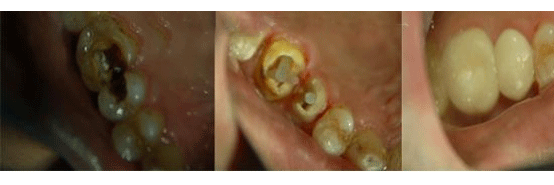

患者:田先生,32岁,主因右上后牙曾行牙髓治疗要求冠修复就诊。

检查:大面积银汞充填,叩痛,不松动,牙龈无明显红肿。

X线片显示:未根充,根尖区牙周膜略增宽。

诊断:慢性根尖周炎。

治疗计划:根管治疗+冠修复。

常规根管治疗:去旧充填物,寻及四根管口,根测,扩孔,NITI预备,冲洗,封药。一周后必兰糊剂+冷侧压根充。预约两周后16冠修复。

根管治疗后两周后:患者右上后牙上次治疗后无明显不适。

经检查发现:16暂封完好,不松动,牙龈无红肿。

与患者协商决定:行16石英纤维桩+氧化锆全瓷冠修复。

术前图片和预备、试桩图片

纤维桩粘接,堆核,牙体预备,排龈